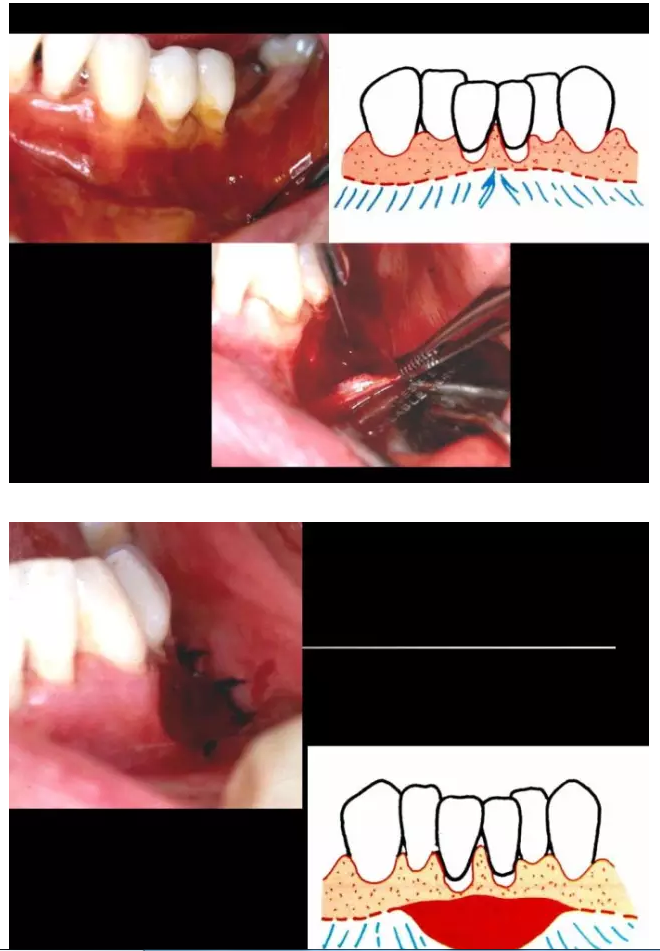

相關(guān)牙周防治